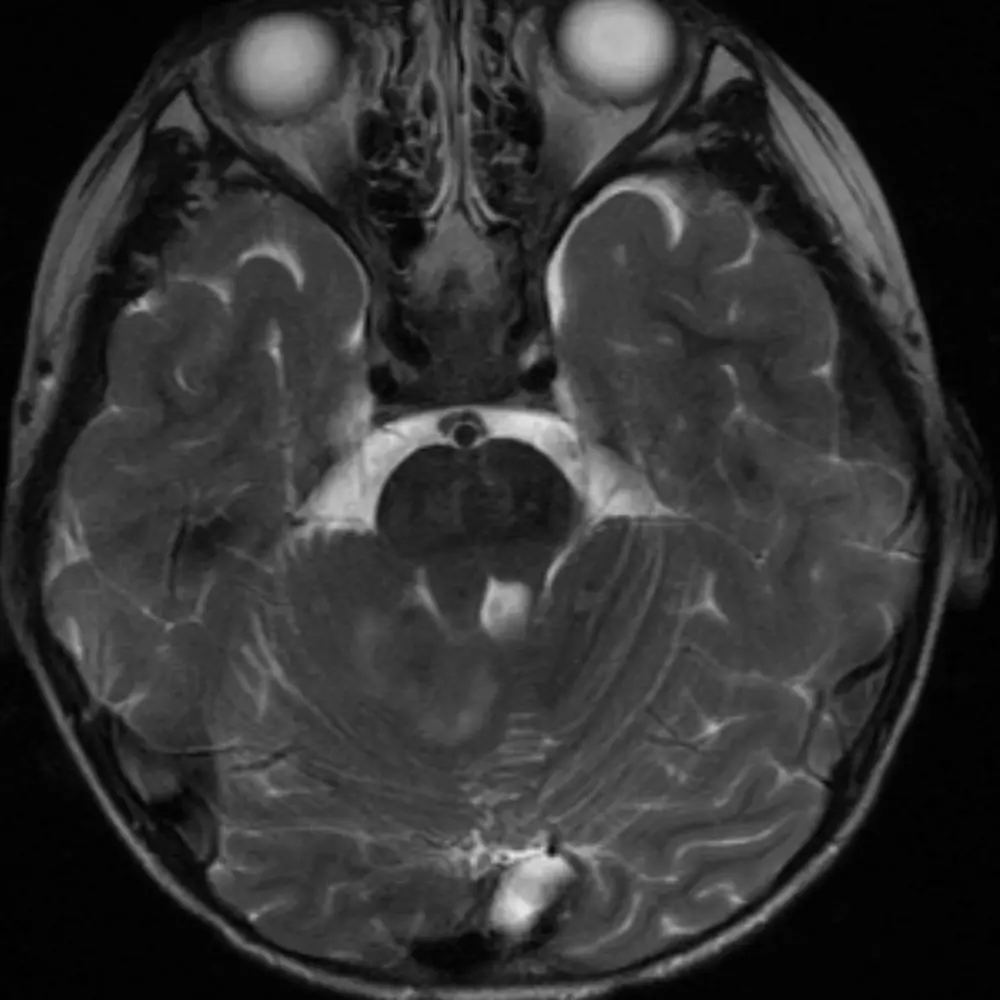

The lateral borders of the medulla are concave compared to the bulbous, convex borders of the pons.

2. Vertebral arteries

The vertebral arteries fuse to form the basilar artery approximately at the level of the upper medulla. If they are present, then you are likely at the level of the medulla in the absence of variant anatomy (e.g. basilar nonfusion).

1. Median aperture

The medulla gradually transitions to the shape of the cervical spinal cord. The median aperture does not significantly change along its course.

The transition of the medulla to the cervical spinal cord is approximated by the foramen magnum. At this point, the medulla is nearly completely round.

1. Vertebral arteries

2. Cisterna magna

The cisterna magna is the largest CSF space in the brain and is located posterior to the lower medulla/cervicomedullary junction. The CSF space lateral to the medulla is called the lateral cerebellomedullary cistern, and the CSF space anterior to the medulla is the premedullary cistern.